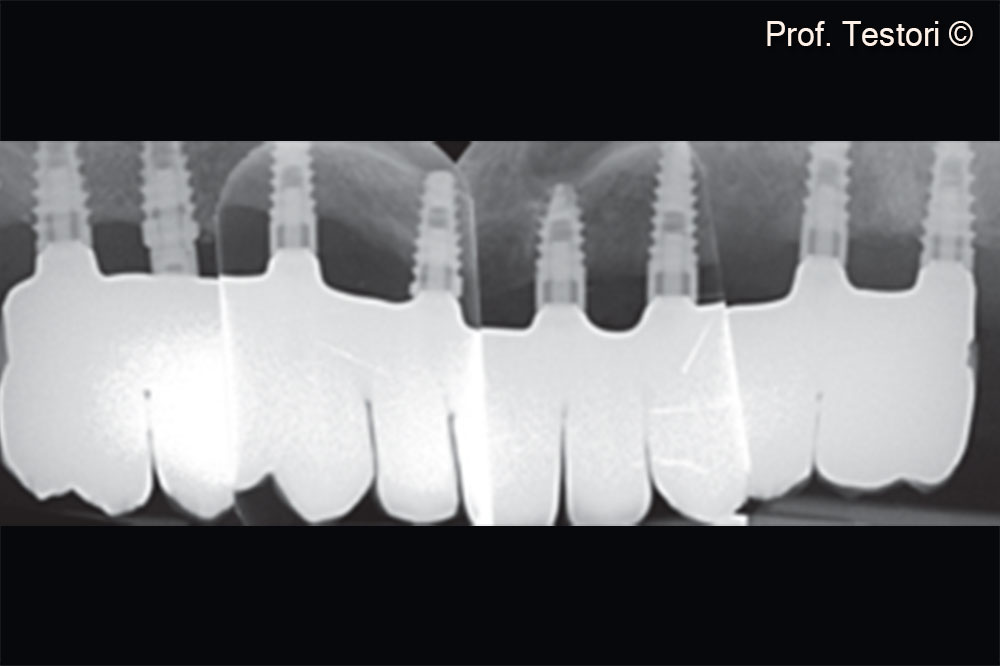

Periapical radiograph of the definitive prosthesis.